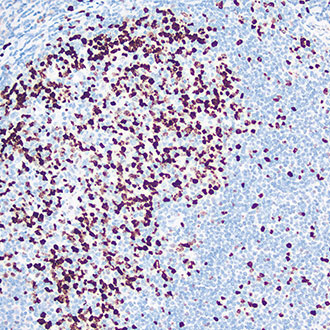

EZH2

EZH2 -